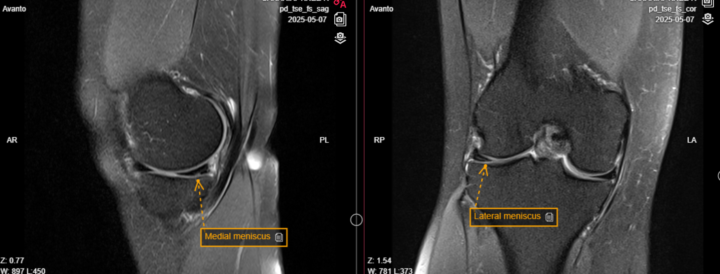

Questionable meniscal hyperintensities.

https://www.cmrad.com/cases/1076527277 61 y female. Pain in medial knee. PD FS sag I do see small MM defect from inferior articular side - is it enough for calling it rupture, mby artifact? What about LM if hyperintensity that looks like degeneration reach articular surface - according Lotysch grade 3 (tear). Balancing in between over and underdiagnosing:)